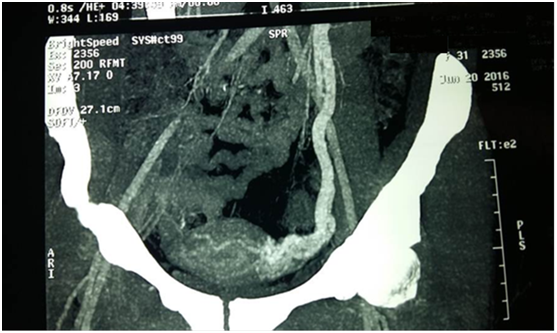

A 24 years old married female Gravida 3para 3 having three children, attended our clinic with a seven months history of recurrent lower abdominal pain associated with feeling of fullness and distention in the lower abdomen exacerbated by menstrual periods and associated with increasing menstrual bleeding. She had no gastrointestinal, neurological or musculoskeletal symptoms, no previous family history of reproductive system disturbances or malignancy (Figure 1).

Figure 1 Case 1 Multi slices Ct Angiography showing dilated pelvic veins extending to Lt Ovarian Vein.

Specific investigation for both patients consisted of Colored Ecko Doppler followed by performance of Multislice Computerized Angiography, proved the presence of pelvic varicosities with dilated Lt Ovarian vein.